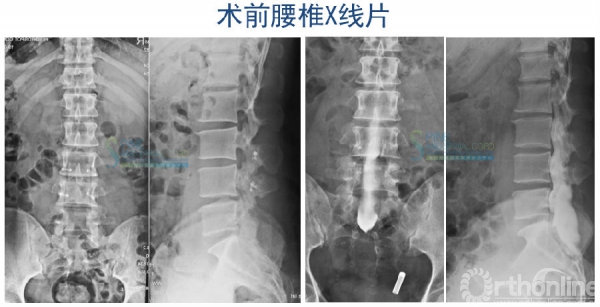

病例一 青少年型TCS

患者女,11岁,双下肢无力伴尿失禁11年

10年前曾行神经松解术

体检:双下肢肌萎缩,左侧马蹄内翻足、鞍区感觉障碍,双下肢反射亢进,babinski征阳性